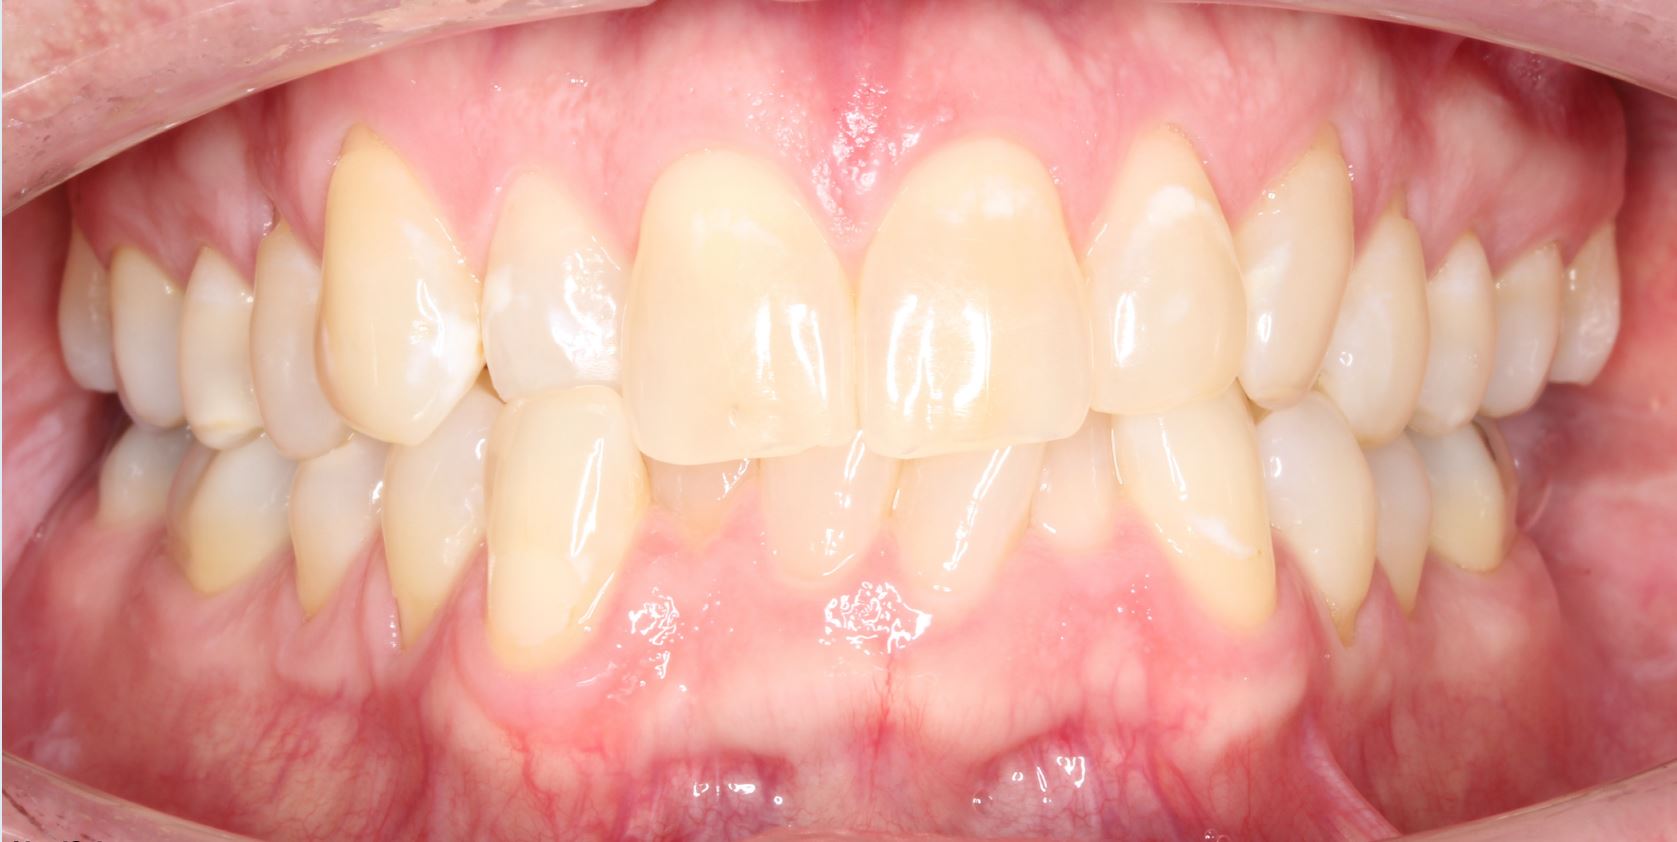

Underbite